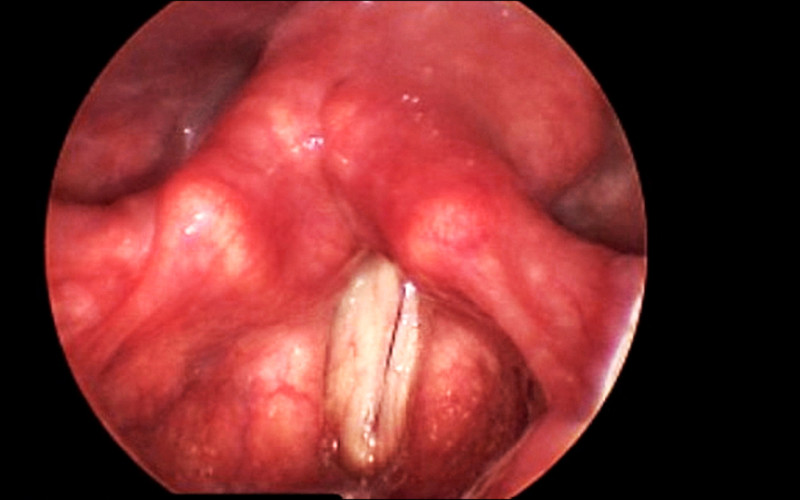

彰基總院長陳穆寬說,患者曾接受甲狀腺手術,術後出現聲音無力、呼吸困難,並伴隨喘鳴聲,內視鏡喉部攝影檢查確定是雙側聲帶麻痺,因患者呼吸道阻塞,伴隨缺氧,院方施予聲帶雷射顯微整形手術,患者術後甦醒時,宛如鬼壓喉嚨的症狀立即消失,呼吸恢復順暢。

陳穆寬指出,正常情況下,雙側聲帶在發聲時閉合,呼吸時張開,讓空氣進入氣管;但患者雙側聲帶麻痺,聲帶無法正常運動,導致氣道狹窄,吸不到足夠空氣,才會出現嚴重喘鳴與呼吸困難症狀。